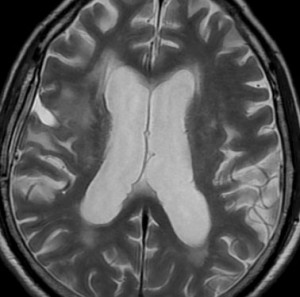

典型的な画像の変化

60代後半の患者さんで右前頭葉転移性脳腫瘍です。けいれん発作で発症しました。

定位放射線治療前

典型的な脳転移のMRIです。腫瘍は,リング状にガドリニウム増強され,内部が腫瘍壊死になっています。腫瘍周囲の脳浮腫がとても強いのが転移の特徴的画像所見(右側のT2強調画像)です。この転移巣に対して,35グレイ・5分割の定位放射線治療が加えられました。

定位放射線治療後

治療は奏功して,腫瘍は縮小して周囲の脳浮腫(右側)も軽減しています。

2年後 放射線壊死の進行

定位放射線治療後約2年,前の画像からはわずか3ヶ月後のMRIです。また右前頭葉の転移病巣が再発したかのように見えます。周囲の浮腫も広がって,左の片麻痺が悪化しました。しかし,ガドリニウム増強されて白くリング状に写る部分が不整形でまわりがギザギザしています。ステロイドを投与しましたが改善せずに悪化傾向を示しました。

手術後の脳浮腫の改善

手術で放射線壊死巣を摘出してから1月半後のMRIです。放射線壊死が摘出されて,脳浮腫もかなり改善しました。同時に右麻痺もよくなってきました。

この例では,アバスチンを投与するという選択肢もあったのですが,医療費が高額で患者さんが経済的に耐えられません。